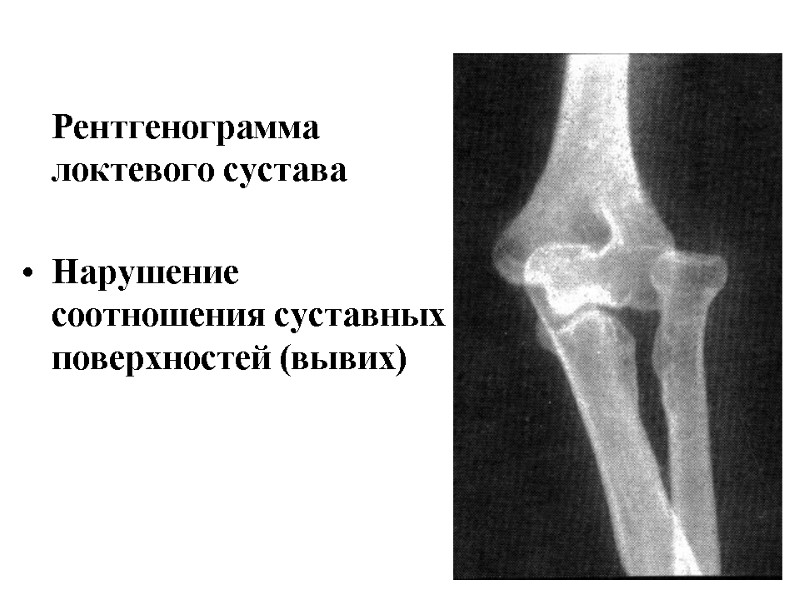

Рентгенограмма локтевого сустава Нарушение соотношения суставных поверхностей (вывих)